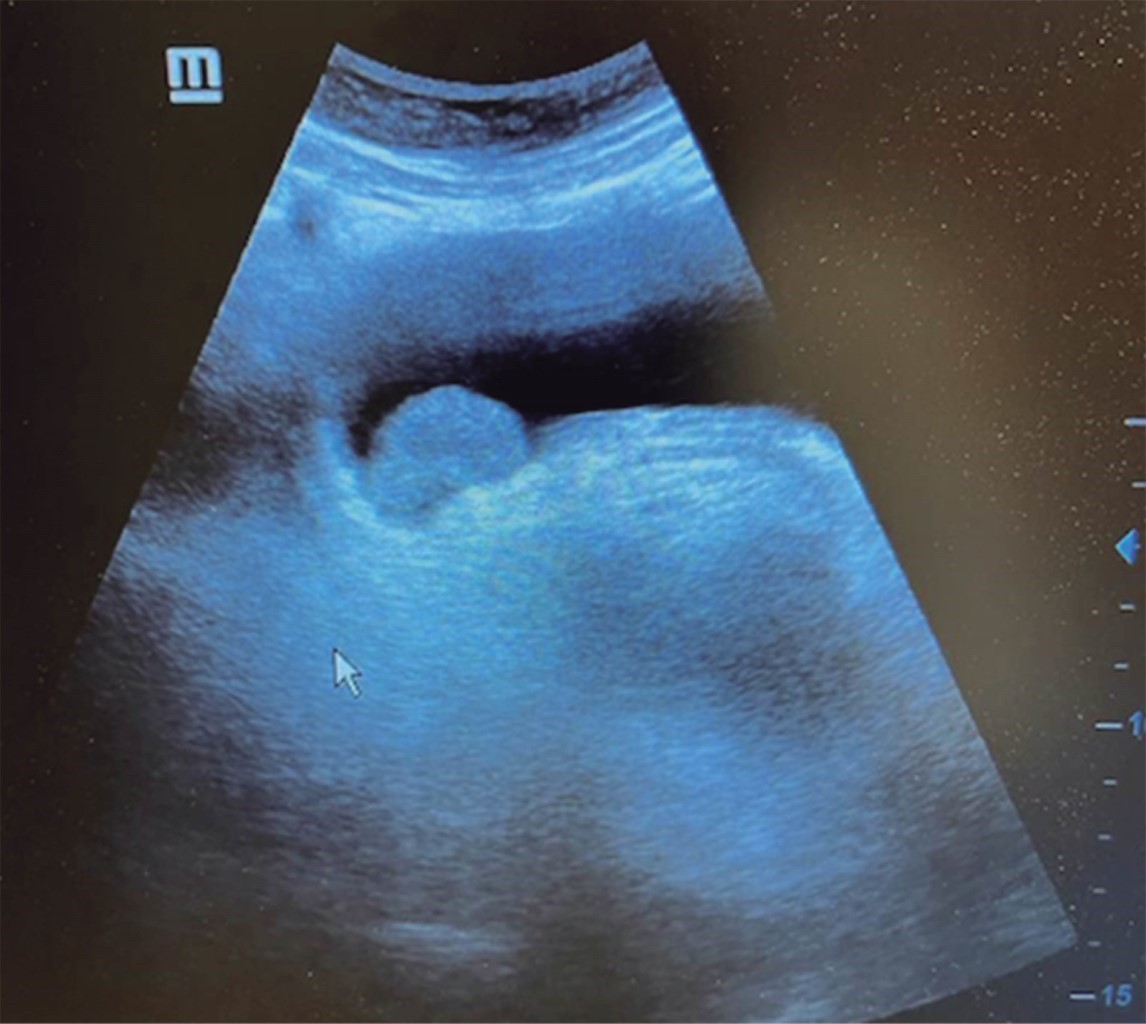

El cirujano general aborda particularmente problemas clínicos que incluyen el aparato digestivo, el cuello, la pared abdominal y los trastornos del sistema circulatorio y el tórax. Un artículo publicado en 2008, por Lindelius,15 demostró que la implementación del ultrasonido por parte del cirujano general en casos de dolor abdominal agudo incrementó en 7.9% la precisión diagnóstica. En la consulta cotidiana de la especialidad, incorporar el rastreo sonográfico al área explorada agrega minutos al examen clínico que aportan datos de notable valor por la objetividad y precisión. El abdomen suele ser el sitio que los cirujanos generales exploramos con más frecuencia. Es posible en una consulta cotidiana hacer todo el protocolo de ultrasonido de abdomen superior en minutos, que incluye ambos cuadrantes superiores y los flancos, pudiendo observar el hígado, la vesícula y los conductos biliares, ambos riñones, el bazo, parte del páncreas y, con ayuda del Doppler color, los principales vasos de la región como la vena cava inferior, la aorta abdominal, la vena porta, los vasos esplénicos y la arteria hepática. Puede haber limitantes como el contenido gástrico, el nivel de llenado de la vesícula biliar o la constitución del paciente y su capacidad de cooperar con el estudio. Pero con la práctica cotidiana, se adquieren las destrezas y el refinamiento suficientes para lograr, con la experiencia acumulada, producir imágenes de relevancia diagnostica inmediata. En la fase de entrenamiento, contrastar nuestros hallazgos con información disponible en la red, con los colegas imagenólogos, o cirujanos ya experimentados en ecografía, permitirá la retroalimentación y la tutoría esenciales de toda curva de aprendizaje. Tradicionalmente se consideraba que aquellos órganos que contienen una mezcla de líquido y gas (intestino, estómago) no son valorables por ultrasonido, el gas produce un efecto rarefacción, ya que no comprime las ondas como un tejido solido o un medio líquido, la señales entonces se dispersan impidiendo que regresen como ecos y permitan al procesador formar una imagen congruente con el órgano explorado. Sin embargo, cuando esta condición cambia como consecuencia de un estado patológico, es posible identificar el contenido intestinal o el gástrico y darnos una idea más aproximada de lo que realmente está ocurriendo en ese abdomen. Podemos, por ejemplo, saber si un estómago está lleno de líquido, o si el intestino contiene residuo sólido, líquido o gaseoso. Los equipos actuales pueden incluso ver en detalle la pared intestinal cuando ésta esté dilatada. Se puede distinguir cuando el colon está ocupado de líquido a nivel del flanco izquierdo como podría ser en una colitis amebiana o en una oclusión intestinal,16 donde se observa dilatación del intestino delgado ≥ 25 mm, el peristaltismo anormal, la presencia de líquido libre intraperitoneal y el edema de la pared intestinal (Figura 2). En casos de dolor abdominal agudo, el ultrasonido puede, en forma inmediata, permitir diagnósticos diferenciales como el hallazgo de una dilatación pielocalicial por nefrolitiasis (Figura 3), o un aneurisma de la aorta abdominal (Figura 4). Un estudio prospectivo realizado en Irvine, California,17 encontró que la a capacidad diagnóstica del médico de primer contacto practicando el ultrasonido para detectar una colelitiasis tiene una especificidad de 87% y una sensibilidad de 82%, mientras que la prueba de ultrasonografía realizada por radiología tuvo sensibilidad de 83% y una especificidad de 86%. Es decir, que, ahorrando tiempo al paciente, el diagnóstico de colelitiasis es factible agregando unos minutos al examen físico inicial. En casos de apendicitis, el método diagnostico considerado como el estándar de oro es la tomografía axial computarizada (TAC). Sin embargo, tiene inconvenientes como su disponibilidad, su costo, el riesgo de radiación en niños y pacientes embarazadas. En tales situaciones, sobre todo en niños, sexo femenino o pacientes delgados, el ultrasonido es una poderosa herramienta que complementa el examen clínico inicial. Las ventajas del ultrasonido frente a la tomografía serian su ubicuidad (ya está en la sala de emergencias), el bajo costo, la ausencia de radiación y el diagnóstico diferencial con causas ginecológicas o genitourinarias de dolor. En apendicitis, la sensibilidad y especificidad de la TAC es de 99.4% y 80.0%, respectivamente. Para el ultrasonido, la sensibilidad diagnóstica es de 83% y la especificidad de 90%. La tasa de apendicectomía negativa es ligeramente mayor en el grupo de TAC que en el del ultrasonido, es decir, 7.1% (3/42) (TAC) en comparación con 4.67% (5/107) (ultrasonido). Hay que recalcar que el ultrasonido es operador dependiente. La experiencia y la calidad del equipo juegan un papel importante.18 La apendicitis tiene varios hallazgos característicos, como la pared edematosa y el aumento de grosor general. Se toman para criterios de positividad una estructura tubular aperistáltica no compresible que mide más de 6 mm de diámetro en el cuadrante inferior derecho (Figura 5).19-21

Figura 2